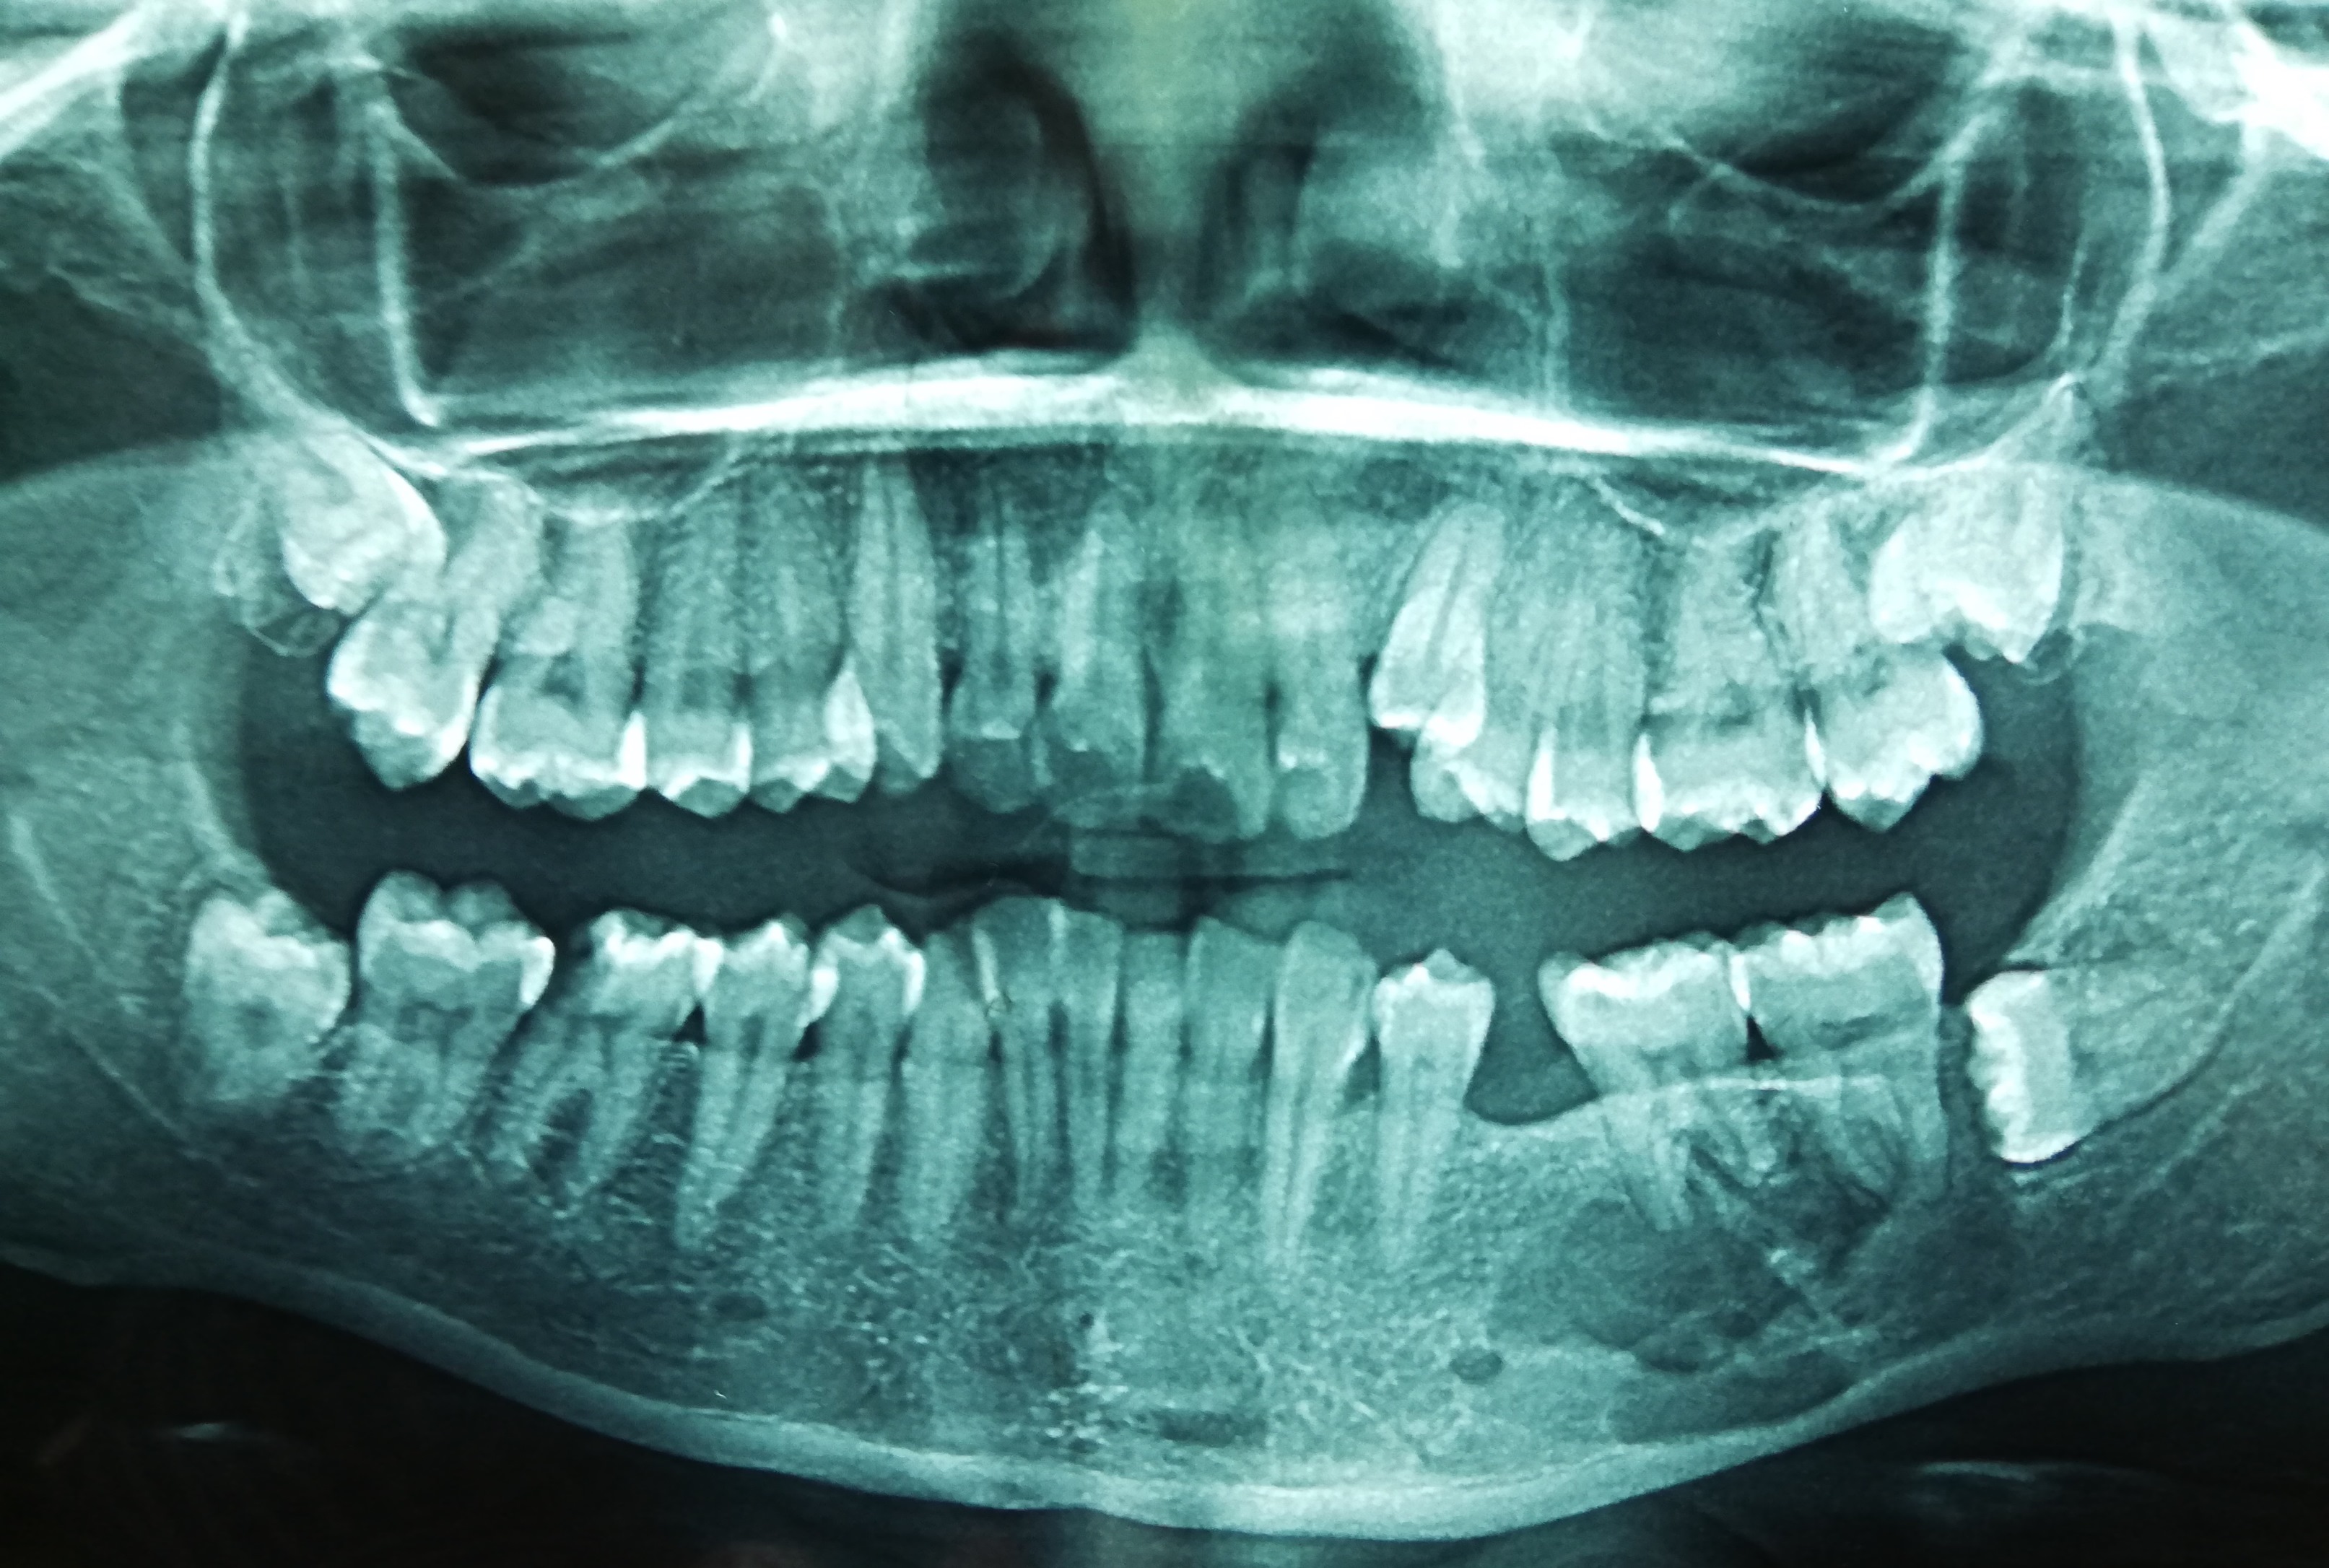

Radiology description

- Plain radiograph: well defined, purely lytic lesions that provoke little reactive bone; the cortex may be thinned and expanded but will not be penetrated (AJR Am J Roentgenol 1993;160:752)

- CT: attenuation values will be in the range of blood and fibrous tissue (Radiol Case Rep 2021;16:2482)

- Angiography (DSA): lesions are usually hypervascular (AJR Am J Roentgenol 1993;160:752)

- MRI: appearance depends on the relative proportion of its components; the lesions, therefore, may be solid, cystic or mixed (Skeletal Radiol 2011;40:205)

- Solid components are intermediate to low intensity on T1 and T2 weighted images, while the cystic components are hyperintense on T2 weighted images and may have fluid-fluid levels

- T1 C+ (Gd): there can be enhancement of the solid component and septa

- Nuclear medicine: bone scan often shows intense uptake (AJR Am J Roentgenol 1993;160:752)